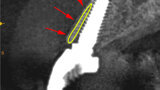

Fig. 27a: The post-op CBCT scan axial view revealed the intact crescent shape of the root membrane (a), as outlined in red in facial to the opaque

implant position (b).

Fig. 27b: The post-op CBCT scan axial view revealed the intact crescent shape of the root membrane (a), as outlined in red in facial to the opaque

Fig. 28a: The post-op cross-sectional view clearly illustrated the position of the implant (a), the definitive restoration located palatal to the root membrane (b),

as outlined in yellow (red arrows).

Fig. 28b: The post-op cross-sectional view clearly illustrated the position of the implant (a), the definitive restoration located palatal to the root membrane (b),